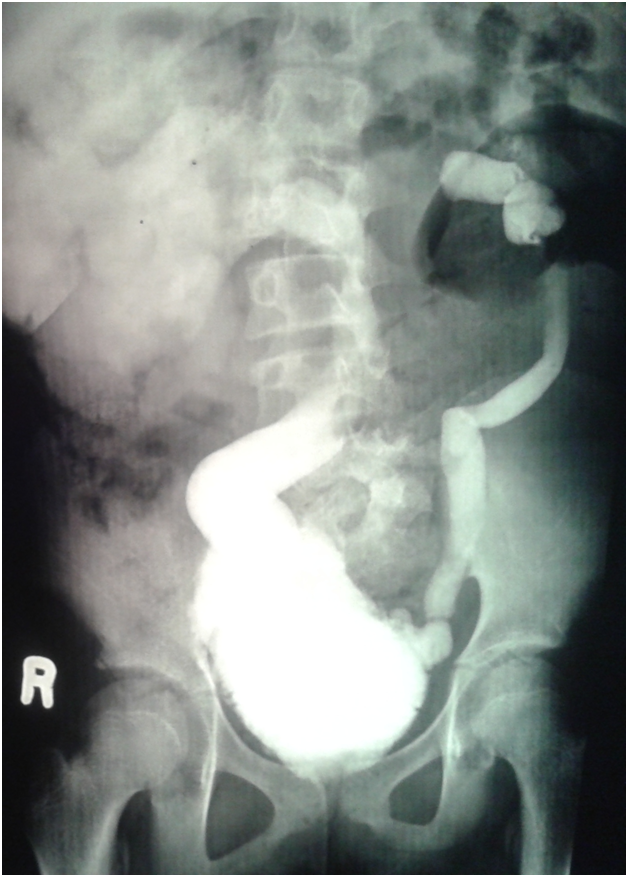

An eleven year old girl was presented to with chronic constipation, persistent dribbling of urine and recurrent urinary tract infections since early childhood. She received treatment by local physicians but remained without proper response. On examination, child was a febrile and her bladder was palpable. Her buttocks were flattened (Figure 1) and external genitalia were wet and excoriated. Anal tone was found decreased on digital rectal examination and the rectum was loaded with hard stool. No definite neurological deficit was found. She was catheterised and stool evacuated with per rectal enema. Her blood analysis showed low haemoglobin (8.1gm %), leucocytosis and raised serum creatinine level (2.2mg %). Urine analysis showed plenty of pus cells and growth of E. coli. Ultrasonography suggested bilateral hydro uretoronephrosis (rt>>lt) with loss of cortico medullary differentiation on right kidney and thickened irregular bladder with significant post void residual urine. Tc-99m DTPA renogram shows poorly functioning right kidney and satisfactorily functioning left kidney. Complete sacral agenesis, 5th lumbar vertebral atrophy and scoliosis with convexity towards right side seen in the control film (Figure 2) while neurogenic bladder with bilateral grade V vesico- ureteric reflux revealed on Voiding phase cystourethrogram (Figure 3). Child was further evaluated with urodynamic study, which suggested an overactive bladder in filling phase (Figure 4). Repeat blood analysis shows (Figure 4) normalisation of serum creatinine (1.2mg %). Her catheter has been removed and she has been placed on self clean intermittent catheterisation along with anti cholinergic (oxy butinine 5mg/daily) and laxative.

Figure 2a Showing bilateral grade V vesico- ureteric reflux.

However, the number of affected vertebrae does not seem to correlate with the type of motor neuron lesion present and the injury appears to be stable and rarely shows sign of progressive denervation.4 Patient may present with constipation, faecal incontinence, urinary incontinence, recurrent urinary tract infections and even kidney damage as neurogenic bladder has to store and empty urine at abnormally high pressure.2 Urodynamic evaluation usually reveals either upper motor or lower motor type of bladder injury, but about 25% of patient may not show any sign of denervation.4 Vesico ureteric reflux may be associated with both types of lesion but more with detrusor over activity.2 Treatment usually consist of anti cholinergic for bladder over activity and CIC with sympathomimetic for underactive bladder.8

Present report is a neglected case of sacral agenesis who presented late at 11years of age. Constipation and urinary incontinence was main complaint and on evaluation she found to have type III sacral agenesis, overactive bladder with bilateral reflux disease leading to kidney injury. High index of suspicion and some clinical clues like flattened buttock and short gluteal folds,9 are helpful for early diagnosis to avoid social stigma of urinary incontinence and to prevent kidney injury.